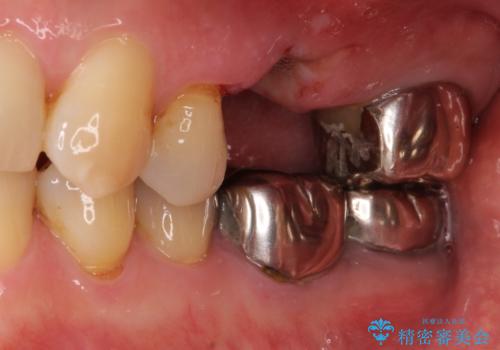

部分矯正を併用した奥歯のインプラント補綴治療

- 奥歯を他院で抜歯した後、インプラント治療を希望とのことで来院された患者様です。

ブリッジの支台を抜歯したことで2本のインプラントが必要であり、その後方はインプラント埋入に必要な骨量が不足していたため、上顎洞粘膜の挙上を行うこととしました。

また、残っている最後方歯は手前に倒れてきていたため、部分矯正により奥に移動させてから、インプラント埋入を行うこととしました。